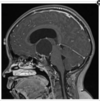

A 16-year-old presents with headaches, nausea, and blurred vision. His neurological examination is remarkable for impaired upgaze and convergence nystagmus. Contrast-enhanced MRI of the brain is shown (figure). Serum beta-HCG and alpha-fetoprotein levels are normal. What is the most likely diagnosis?

a. Endodermal sinus tumor

b. Embryonal carcinoma

c. Choriocarcinoma

d. Meningioma

e. Germinoma

Germinoma